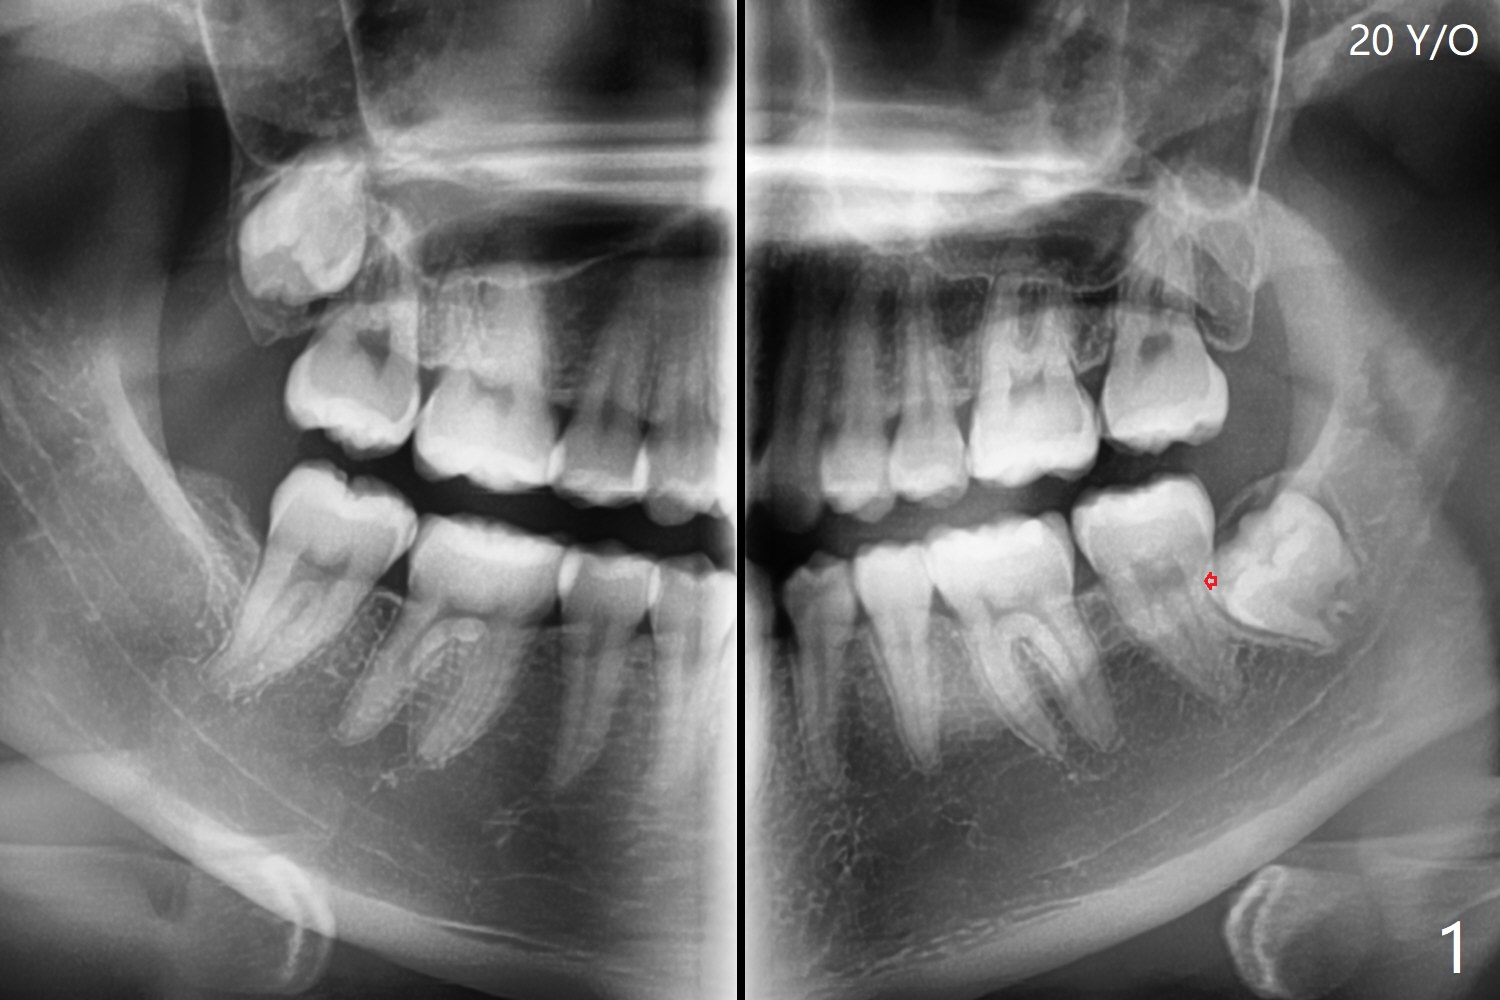

A 20-year-old woman requests extraction of the lower left 3rd molar (Fig.1). In fact the tooth being buccal to the 2nd molar is ignored preop (Fig.1,2 red arrow). The vertical incision is placed too distal with subsequent elevation of the mesial flap. From now on every panoramic X-ray should be viewed with magnification before surgery! After extraction, one piece of Osteogen Plug is placed; the anterior end of the Internal Oblique Ridge (Fig.2 I) is located in the posterior of the socket. As the socket heals, the anterior end of the ridge is expected to advance.